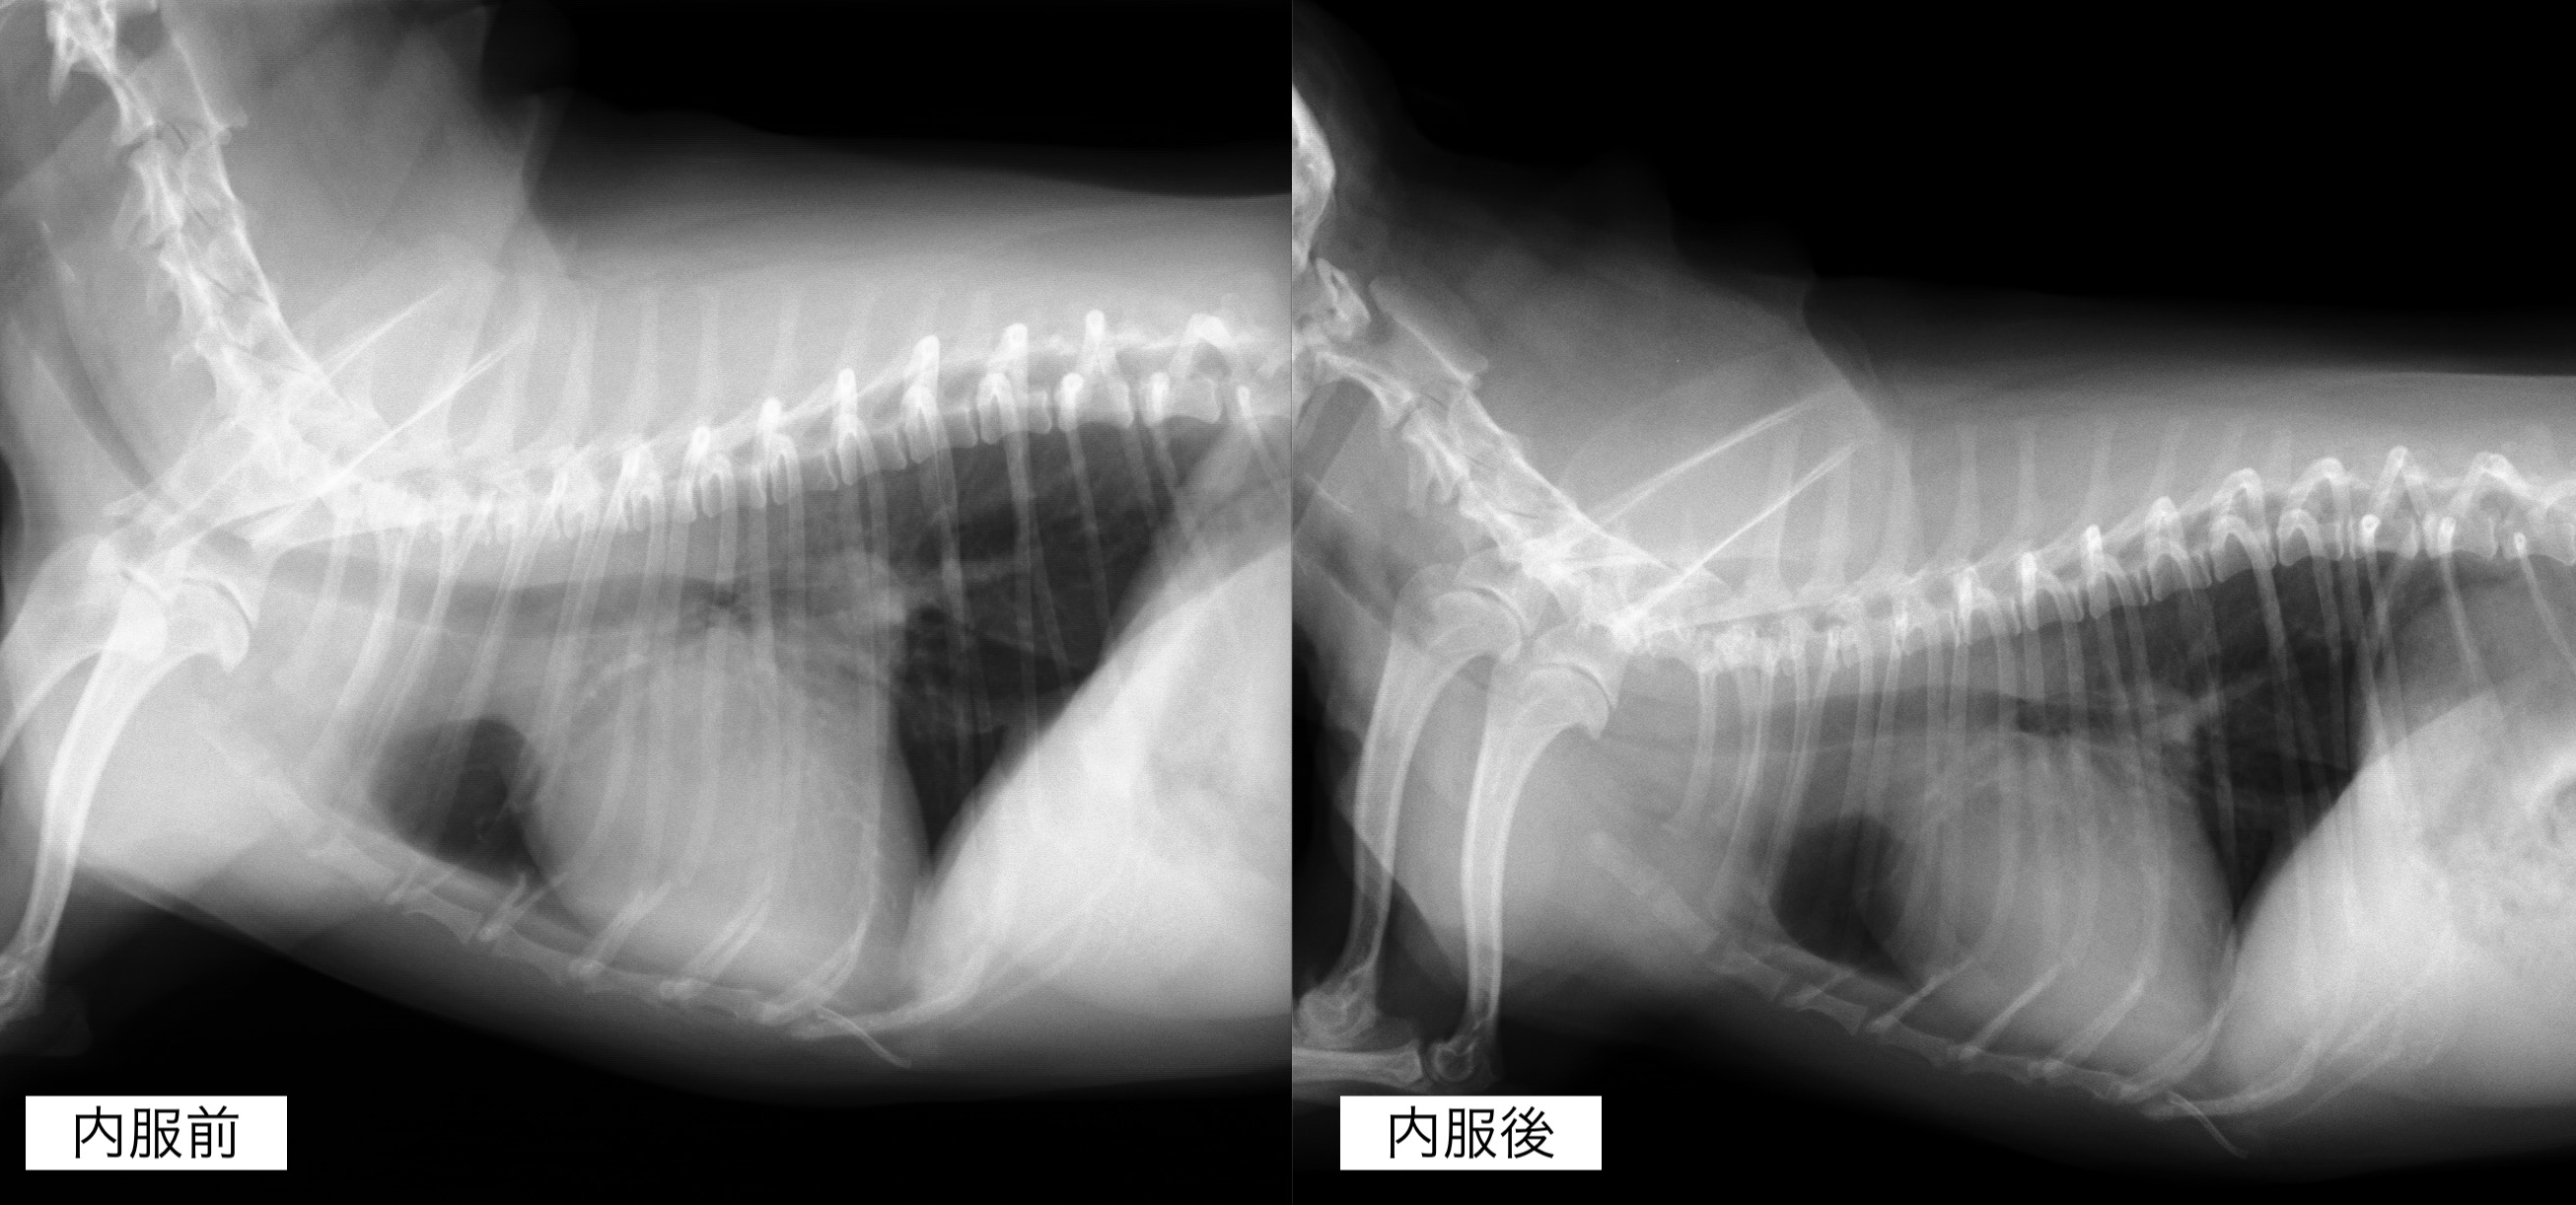

内服開始1ヶ月後のレントゲン検査です。

心臓の拡大はやや改善しており、咳の頻度も減っているとのことでした。